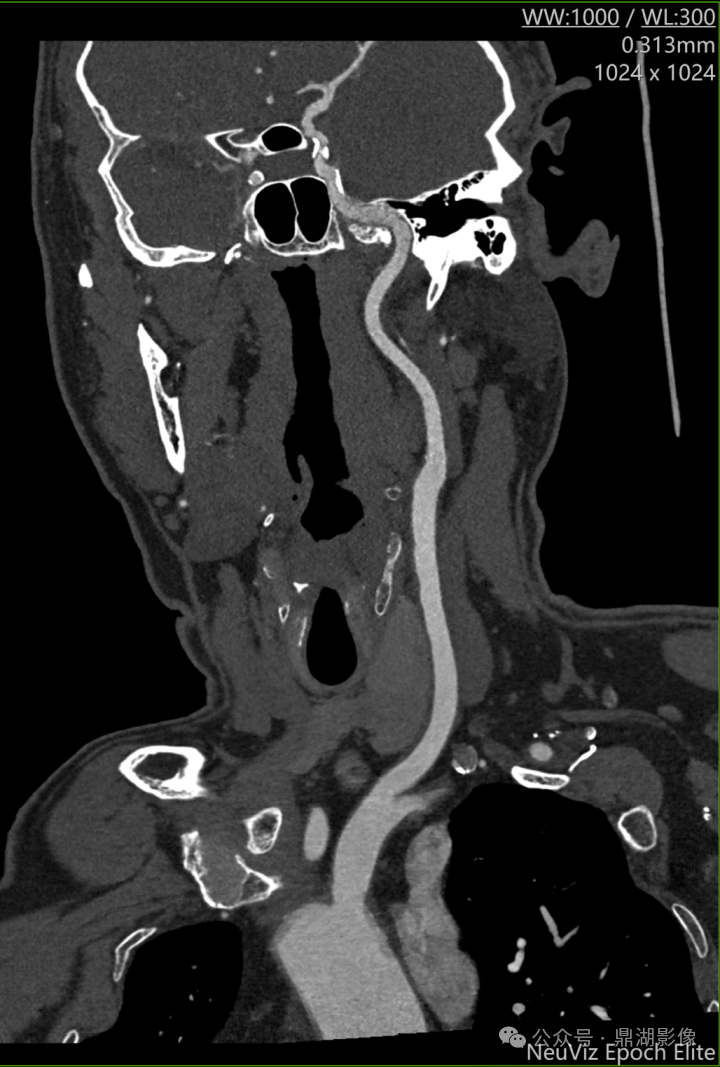

图 头颈CTA扫描曲面重建(CPR)显示:右侧颈内动脉虹吸段血管壁钙化斑块

CT高清扫描在头颈部血管疾病中兼具解剖与功能评估优势,是脑血管病筛查、诊断及治疗规划的核心工具,NeuViz Epoch Elite超高清模式可更精细的显示头颈部血管的解剖结构复杂,包括颈动脉、椎动脉、Willis环等结构。